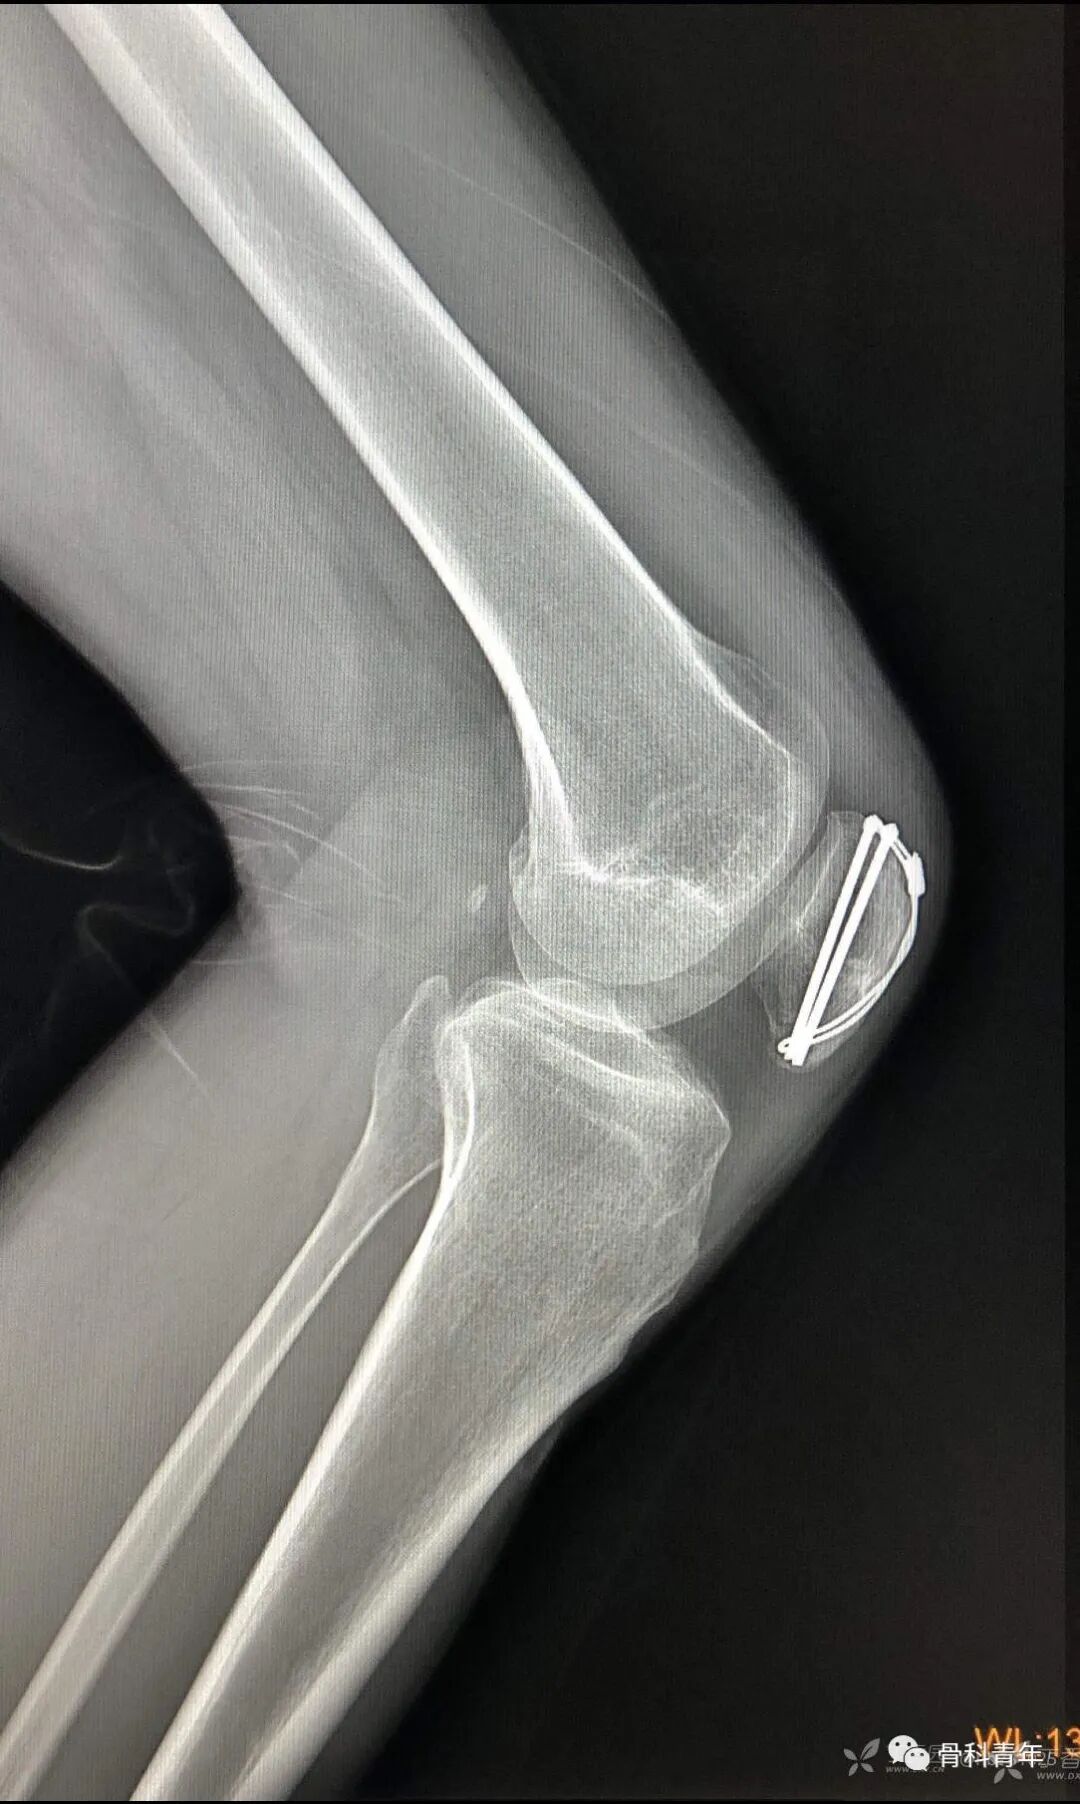

23.尺骨鹰嘴骨折

24.桡骨小头骨折